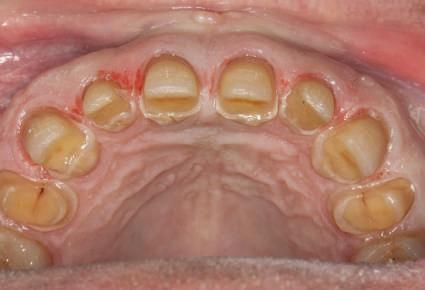

Cazul (3): Refrezarea bonturilor individualizate

Figurile

9. Bonturile de vindecare.

10. Bonturile individualizate în prima etapă.

11. Recesia evidentă în jurul bonturilor din prima etapă, după extracţiile adiacente şi inserarea implanturilor din faza a doua.

12. Bonturile refrezate şi noile bonturi individualizate.